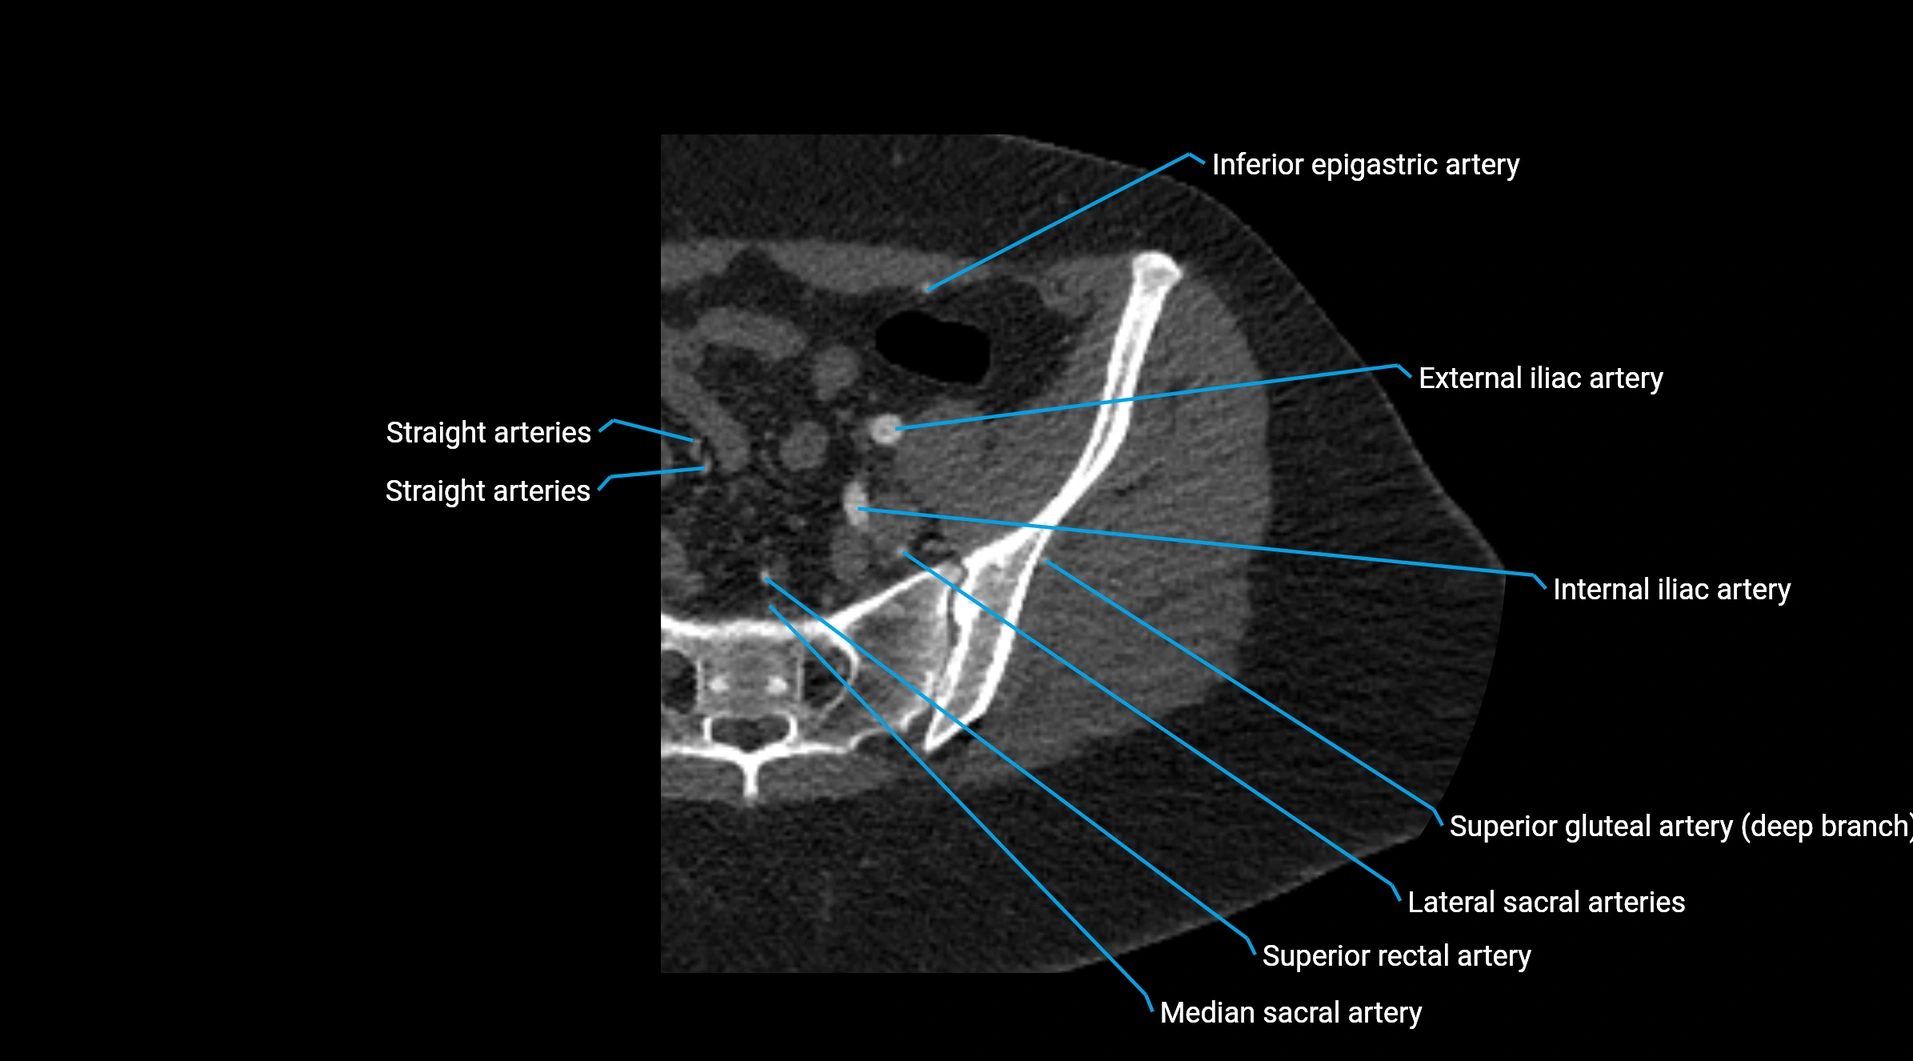

Contrast-enhanced CT (CTA):

• Gold standard for abdominal aortic imaging

• Provides excellent detail of lumen, wall, aneurysm, thrombus, and branch vessels

• Multiplanar and 3D reconstructions help in aneurysm measurement, stent graft planning, and dissection evaluation

• Detects acute rupture, traumatic injury, or occlusion with high sensitivity